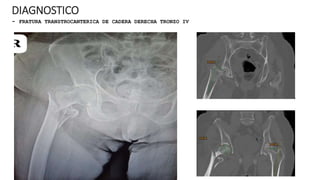

DIAGNOSTICO

- FRATURA TRANSTROCANTERICA DE CADERA DERECHA TRONZO IV

PLAN QUIRURGICO 06/06/24

- ARTROPLASTIA PARCIAL DE CADERA DERECHA

CONTROL DE RX POST QUIRURGICOS 04-06-24